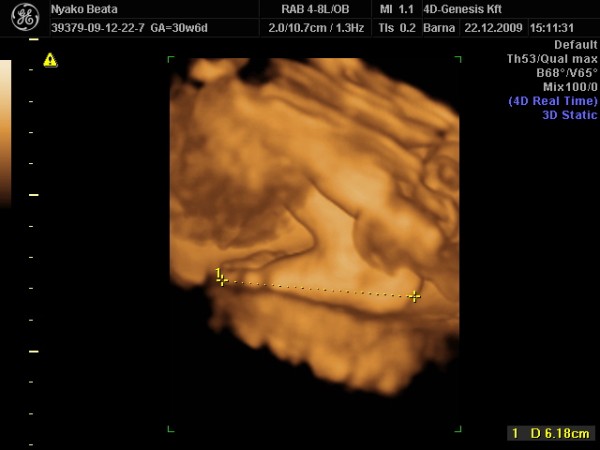

Mariann, szepen kerekedik a pocid!